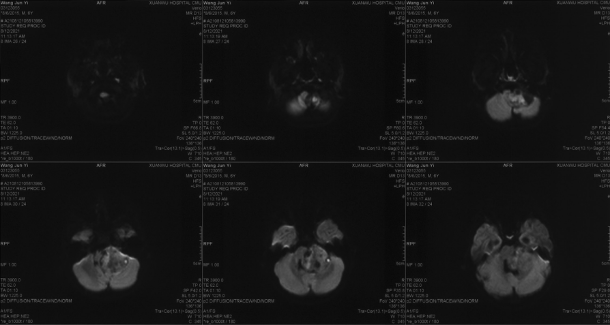

Preoperative MRI-DWI